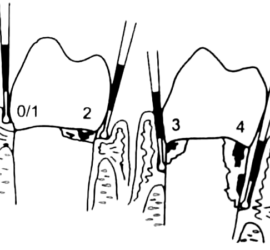

Зубы штифтовые — получили название от способа крепления в корневом канале путем введения в него металлического стержня-штифта. Основными частями этих протезов являются штифт, входящий в канал корня, и искусственная коронка зуба. Показанием для применения штифтовых зубов является полное разрушение коронки, но хорошо сохранившийся и устойчивый корень, канал которого может быть […]